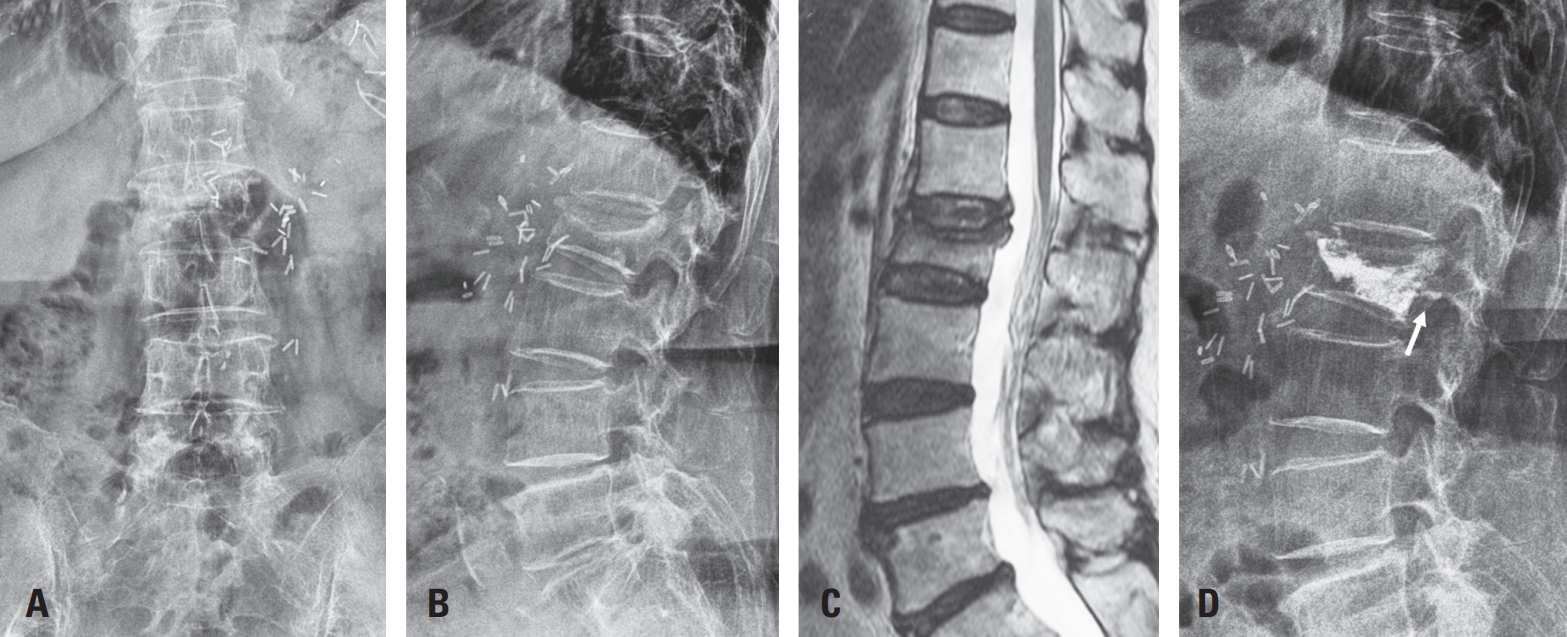

A 78-year-old woman with a history of hypertension, hyperlipidemia, and two prior aortic surgeries for aortic dissection had undergone mechanical aortic valve replacement and was on long-term warfarin therapy (2.5 mg daily). She presented with lower back pain and was diagnosed with an L2 compression fracture, initially managed conservatively (Fig. 1AC).

Due to persistent symptoms, kyphoplasty was performed after discontinuation of warfarin and bridging with enoxaparin. The procedure was uneventful, though postoperative X-ray showed mild posterior cement leakage (Fig. 1D). Enoxaparin (50 mg twice daily) was resumed for anticoagulation.

Fig. 1.

(A–C) Sagittal and axial T2-weighted MR images and lateral radiograph demonstrating acute L2 compression fracture. (D) Postoperative lateral radiograph showing mild posterior cement leakage (white arrow) following kyphoplasty.

Fig. 1. (A–C) Sagittal and axial T2-weighted MR images and lateral radiograph demonstrating acute L2 compression fracture. (D) Postoperative lateral radiograph showing mild posterior cement leakage (white arrow) following kyphoplasty.